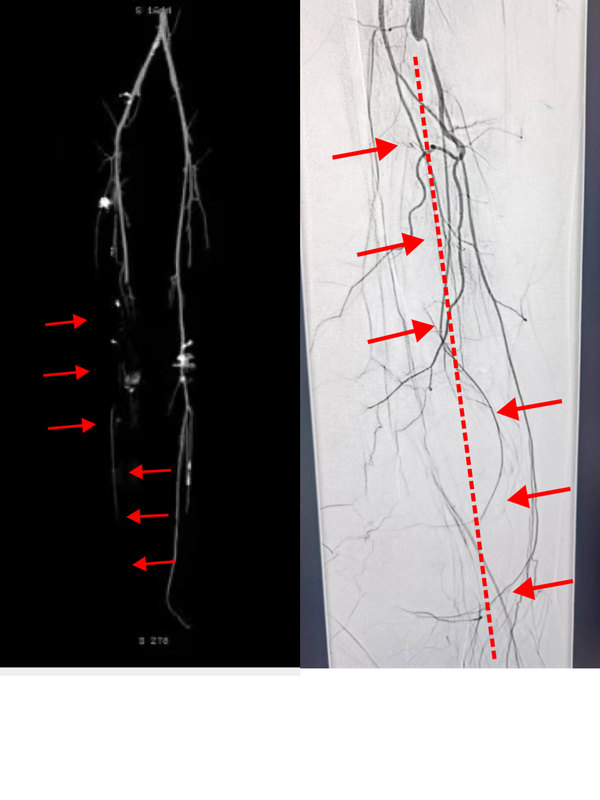

脈管炎患者的福音:哈醫(yī)大四院血管外科成功開展準分子激光應用于下肢血栓閉塞性脈管炎的治療

近期,哈醫(yī)大四院血管外科利用準分子激光斑塊消蝕聯(lián)合藥物涂層球囊技術,成功為一例年輕血栓閉塞性脈管炎患者開通閉塞動脈,挽救肢體。患者李某今年32歲,半年前自覺右下肢麻木伴疼痛,一個月前麻涼痛癥狀加重,并逐漸出現(xiàn)了右足跟潰爛發(fā)黑的癥狀?;颊呒凹覍僮咴L了省內(nèi)多家醫(yī)院,醫(yī)生給出了相同的建議:截肢?;颊呒捌淠赣H難以接受余生在輪椅上度過的現(xiàn)實,經(jīng)多方打聽來到哈醫(yī)大四院血管外科就診。黃任平主任經(jīng)過仔細詢問病史,查體,閱讀影像資料后,考慮患者患有血栓閉塞性脈管炎。對于脈管炎的患者并伴有足破潰,如不及時治療,患者截肢幾率非常大。傳統(tǒng)經(jīng)皮動脈球囊擴張成形術(PTA)難以解決長段、閉塞性、炎性增生病變,施行PTA后容易出現(xiàn)血管壁彈性回縮、殘余管腔重度狹窄等。支架的植入也會出現(xiàn)術后急性閉塞和再狹窄發(fā)生,跨關節(jié)病變支架植入術后極易出現(xiàn)支架扭曲、斷裂等現(xiàn)象。正逢哈醫(yī)大四院血管外科引進我省第一臺用于治療下肢血管病變的準分子激光設備,是目前國內(nèi)外十分推崇的腔內(nèi)減容技術。黃任平主任決定用這臺新設備為年輕小伙手術治療,術中黃任平主任首先用準分子激光開通閉塞的血管,然后應用載藥球囊對病變部位進行擴張,手術順利結束。術后下肢動脈血流即刻恢復,目前患者恢復良好,右下肢疼痛涼麻癥狀消失,潰爛部位逐漸好轉。此次哈醫(yī)大四院血管外科采用的準分子激光斑塊消蝕技術在國外已經(jīng)有20多年的應用歷史,技術已然成熟,但在我國起步較晚,在我省尚屬首次應用。它主要通過三種方式來發(fā)揮作用:一是光消蝕作用,主要把物質分子裂解;二是聲壓波效應,主要作用于較硬的動脈硬化斑塊,將其震碎;三是空泡效應,主要是將這些斑塊碎屑組織粉碎成比紅細胞還小的納米級別,因而不會對遠端血管造成栓塞。而且,激光減容技術相對斑塊旋切等其它減容技術,對血管壁的損傷更小。黃任平醫(yī)學博士、博士后,碩士生導師哈爾濱醫(yī)科大學附屬第四醫(yī)院血管外科主任??專業(yè)方向:擅長血管外科的常見病多發(fā)病的診治,從事微創(chuàng)血管病治療與創(chuàng)面治療10余年,治愈各種靜脈曲張、糖尿病足、下肢靜脈血栓、脈管炎、動脈硬化閉塞癥、胸腹主動脈瘤、動脈栓塞、肺栓塞、鎖骨下動脈閉塞、腎動脈狹窄、嬰幼兒血管瘤、血管畸形等近20000例。血管外科門診出診醫(yī)生一覽表出診醫(yī)生出診時間黃任平周一、周二上午8:00-11:30李佳樂周一、周二下午13:00-16:30謝春楊周三、周四上午8:00-11:30馬文超周五上午8:00-11:30出診地點:哈爾濱醫(yī)科大學附屬第四醫(yī)院門診三樓C區(qū)外科3診室咨詢電話:0451-82576869